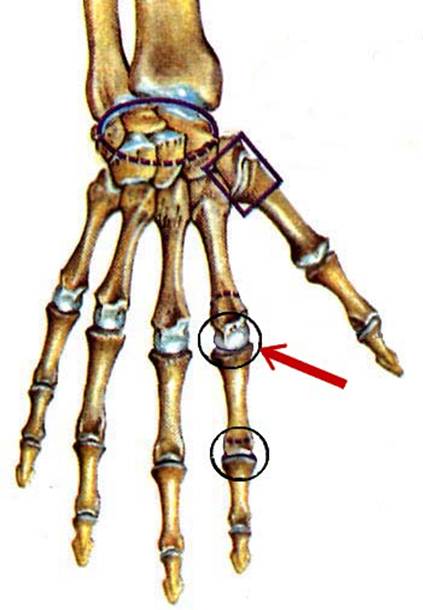

S: Числом 10 обозначена os trapezium (латинский язык).

S: Цифра 5 обозначает ossa metacarpi (латинский язык).

S: Цифрой 8 обозначена os capitatum

S: Числом 12 обозначена os scaphoideum

S: Числом 13 обозначена os triquetrum

S: Цифра 3 указывает на phalanx proximalis

S: Цифра 2 указывает на phalanx media

S: Цифра 1 указывает на phalanx distalis

S: Стрелка указывает на art. Radioulnaris distalis

S: Стрелка указывает на art. Radiocarpalis

S: Стрелка указывает на art. Mediocarpalis

S: Стрелка указывает на art. Carpometacarpalis

S: Стрелка указывает на art. Metacarpophalangea

S: Стрелка указывает на art. Interphalangea manus